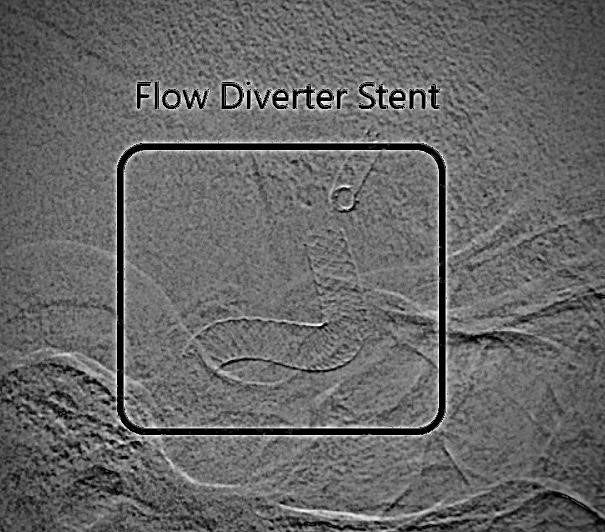

Subsequently, the M1 segment of the right middle cerebral artery (MCA) was catheterized, and a flow diverter stent was used to bridge the neck of the cavernous aneurysm (Figures 3). This resulted in the successful redirection of blood flow and subsequent stasis within the aneurysm sac.

Figure 3. Flow divert stent in the right MCA.